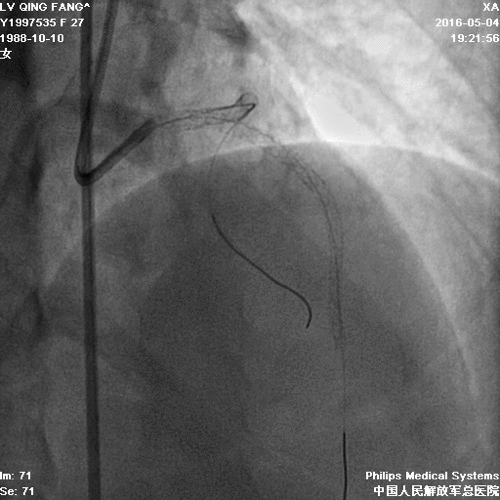

造影

PCI